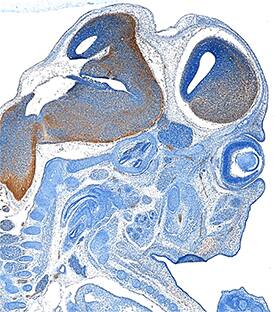

PD-ECGF/Thymidine Phosphorylase antibody in Mouse Embryo by Immunohistochemistry (IHC-Fr).

PD-ECGF/Thymidine Phosphorylase in Mouse Embryo.

PD-ECGF/Thymidine Phosphorylase was detected in immersion fixed frozen sections of mouse embryo (15 d.p.c.) using Rat Anti-Human/Mouse/Rat PD-ECGF/Thymidine Phosphorylase Monoclonal Antibody (Catalog # MAB7568) at 25 µg/mL overnight at 4 °C. Tissue was stained using the Anti-Rat HRP-DAB Cell & Tissue Staining Kit (brown; Catalog # CTS017) and counterstained with hematoxylin (blue). Specific staining was localized to developing brain. View our protocol for Chromogenic IHC Staining of Frozen Tissue Sections.